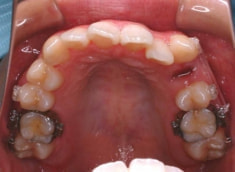

治療後(2年6ヶ月後)

治療後のパノラマレントゲン

上顎8番は抜歯済み、下顎8番は後方余地に余裕がでたので、今後抜歯を行う予定です。